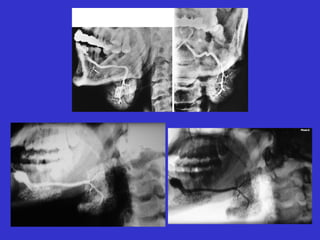

Este documento describe las diferentes proyecciones radiográficas utilizadas para examinar los senos paranasales, incluyendo las proyecciones básicas de Caldwell, Waters lateral y las proyecciones especiales como Hirtz y Waters mentonasal. También describe las diferentes estructuras anatómicas que componen el complejo ostiomeatal anterior y posterior de los senos paranasales.